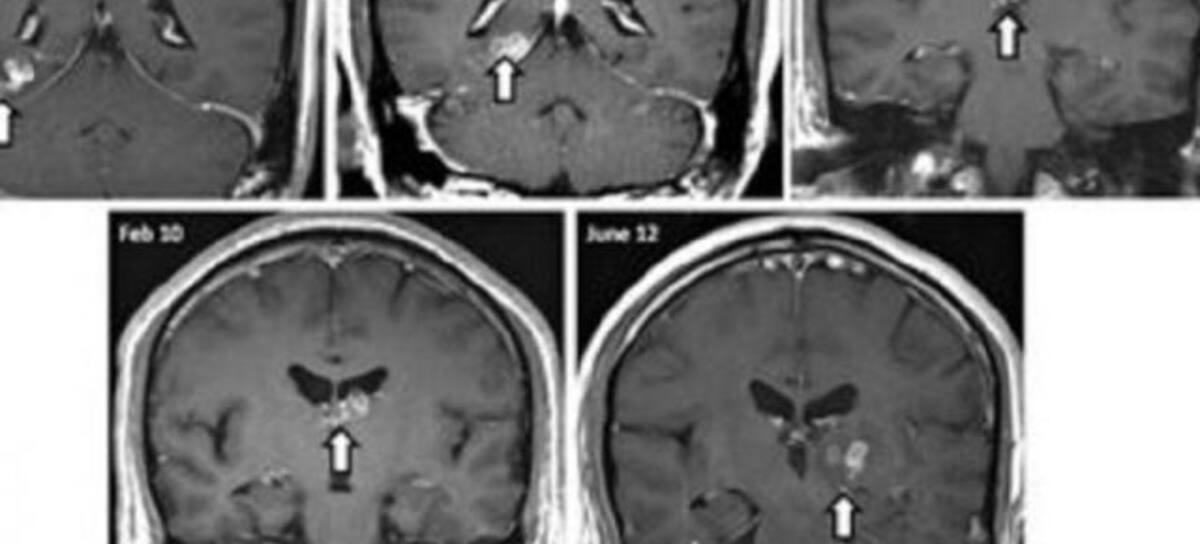

El parásito había escavado de un lado del cerebro al otro, según ha publicado The Guardián y ha recogido NY daily news.

El gusano, que normalmente se encuentra solo en China, fue descubierto cuando los doctores realizaron una biopsia al hombre de 50 años. Se cree que el paciente puede haber cogido el parásito en una visita a China, pero lo que aún no se sabes es cómo llegó a infectarse.